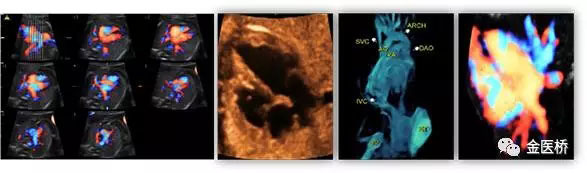

胎兒心臟超聲又名胎兒超聲心動圖,是一種無創(chuàng)、安全的影像學檢查,也是胎兒期唯一有效的能夠顯示胎兒心臟結(jié)構(gòu)、血流及評估心臟功能的影像學手段,在產(chǎn)前及時診斷,隨診,預(yù)后判斷至關(guān)重要,不可替代。